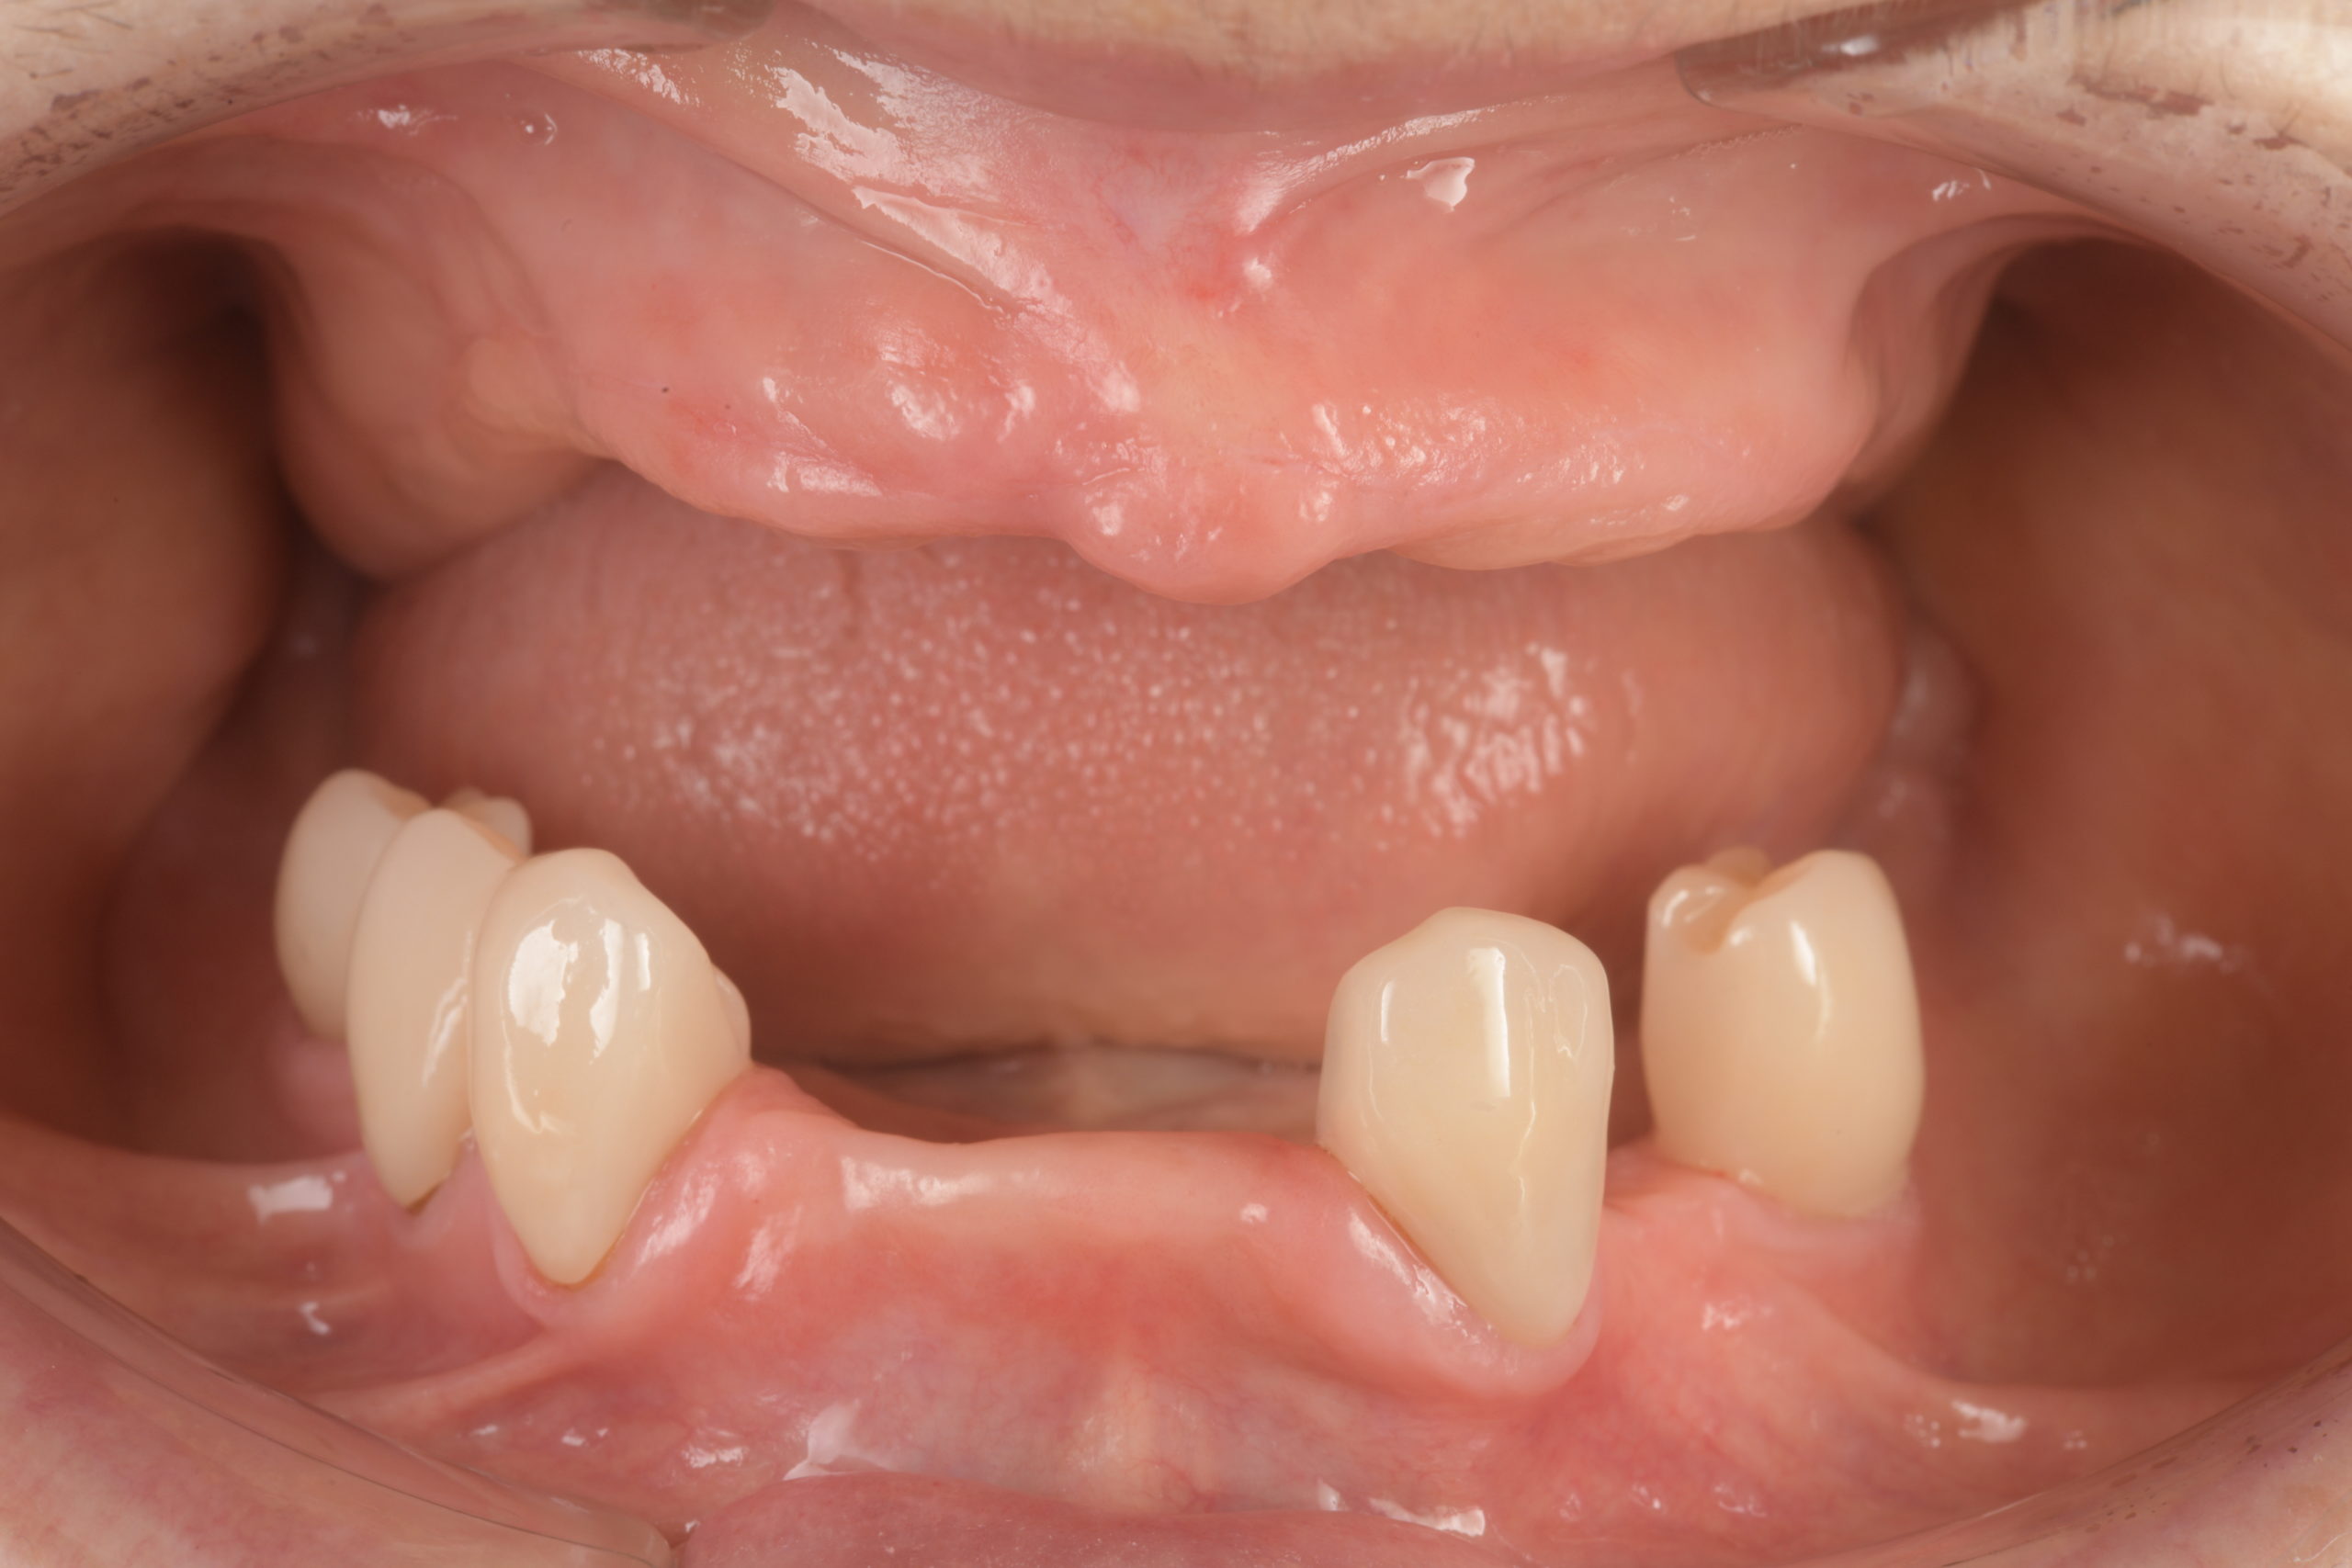

患者様は70代女性。左下の奥歯の痛みと義歯の作り直しを希望され来院されました。義歯の作り直しについては、できるだけ違和感のないもので、かつ見た目も綺麗な口元にしたいとのご要望がございました。 左下の奥歯は重度の歯周病のため抜歯を行い、その後残りの歯をセラミッククラウンにて補綴し、上下の金属床義歯を作製致しました。 治療後の経過は良好で、患者様より「上の入れ歯も下の入れ歯もピタッとしていて非常に快適です。上の入れ歯は以前のように食事中落ちてくることもなく非常に食べやすいです。見た目も綺麗な口元になり非常に満足しています。ありがとうございました。」とのお言葉をいただきました。 当院ではこのような機能的、審美的に良好な精密義歯治療に力を入れております。お気軽にご相談ください。 |

治療後(義歯装着時)